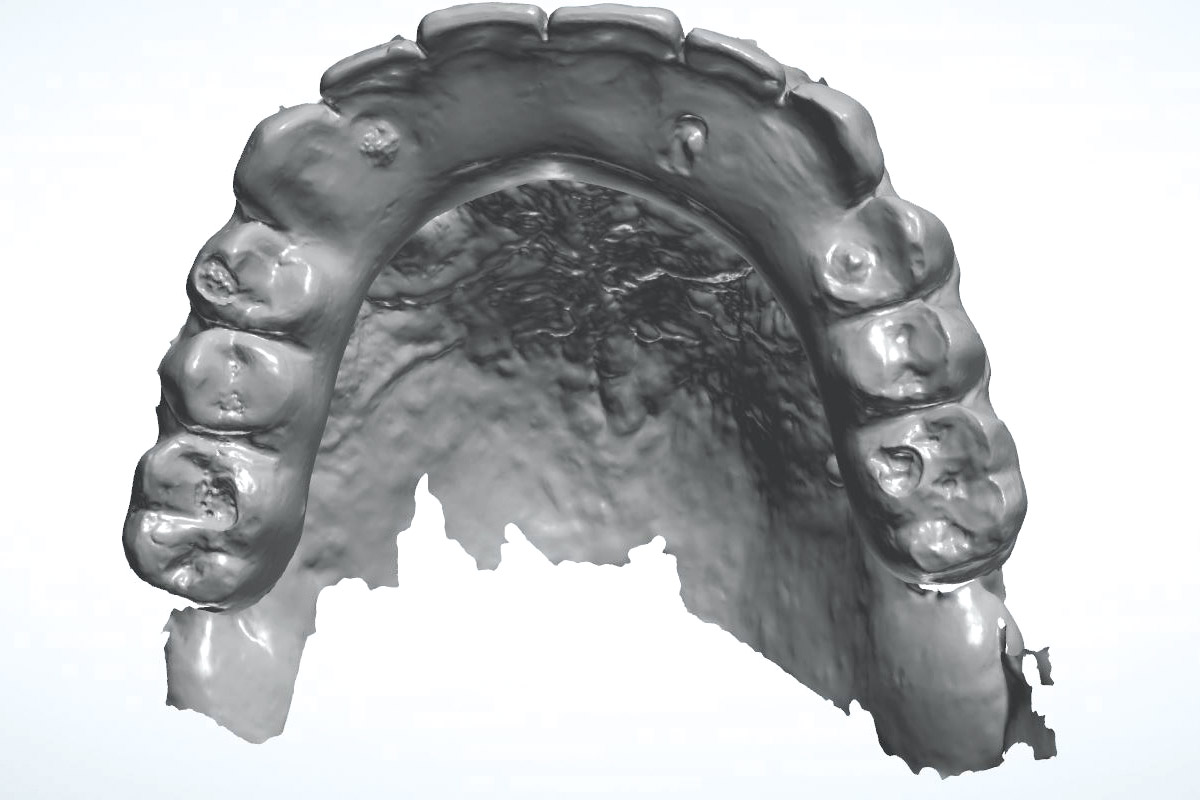

Full maxillary reconstruction with maxgraft® bonebuilder - Dr. C. Hilscher

Reconstruction of Anterior Maxilla with maxgraft® bonebuilder – Dr. B. Han